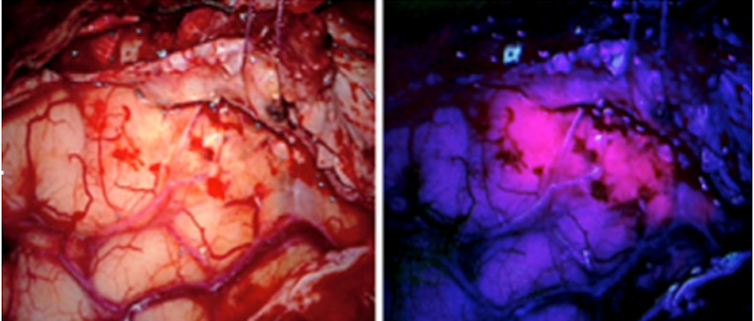

Tumeur colorisée en rose

Pour le traitement du glioblastome, cancer du cerveau au pronostic très sombre, un essai clinique a été mis en place en mai 2017 à Lille. A ce jour 9 patients ont été traités par thérapie photodynamique. La technique consiste à faire boire au patient, 5 heures avant l’intervention chirurgicale, une substance qui va permettre de guider le neurochirurgien lors de la résection de la tumeur. En effet, cette substance est spécifiquement accumulée dans les cellules tumorales. Au bloc chirurgical, le chirurgien utilise son microscope avec une lumière bleue afin de mieux voir la tumeur qui apparaît en rose. Un ballonnet, développé par l’unité Oncothai, est ensuite introduit dans la cavité obtenue après chirurgie. Une illumination en lumière rouge permet alors de détruire alors les cellules tumorales résiduelles situées en périphérie de la cavité. Il faut souligner que c’est la première fois que la PDT est proposée en première intention thérapeutique pour le glioblastome. Jusqu’à maintenant, les quelques essais réalisés étaient proposés après récidive.